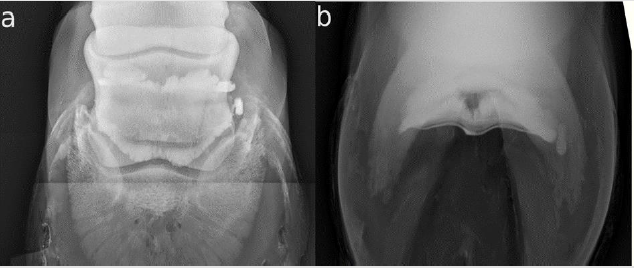

Horse 12 was lame (1-2/5) in the right front limb. After the positive distal digital nerve block with a shift of lameness to the left side and no findings in ultrasound and X-ray, a bursography was performed. The bursography showed an accumulation of CM medial to the navicular bone in both views (Figures 4a & 4b). In the DPr-PaDiO CE view, there was also a little bit of pooling of CM lateral to the ridge of the navicular bone. After the injection, the horse had acute lameness in a few steps (4/5). This lameness was gone after four hours and a single dose of flunixin-meglumin. The horse was diagnosed with a suspected traumatic rupture of the NB. The contralateral limb was also injected and showed no findings. It was given a good prognosis. After eight weeks rest and rehabilitation training, the horse was complete sound. There was a very clear end of the proximal dye column in the lateral and the DPr-PaDiO view (Figures 5a & 5b) in 4/23 (17.39 %) legs compared to the other legs (Figures 5c & 5d). In the lateral view, there was also a radiolucent area in the bursa, which seems to be air from the injection. Therefore, the air presents the proximal border of the NB. Three out of these four legs received 10 mg/1ml triamcinolonacetonide.

Figure 4: CE X-rays of horse 1,2 right front; lateral is to the left

a. The DPr-PaDiO X- ray shows that the proximal border of the NB has two outer pouches with normal invaginations, which

represent the normal synovium of the NB. It is nearly the same in the distal border of the NB. Except for the pooling of CM on

the medial site of the navicular bone, this seems to be a normal NB. The CM medial to the bursa has to be a small rupture of

the NB;

b. The finding is reproducible in the DPr-PaDiO X-ray. In addition, a small pooling of CM lateral to the ridge of the navicular

bone is visible

Figure 5:

A. a) DPr-PaDiO X- ray of horse 4; lateral is to the left. This shows a nearly horizontal and smooth proximal border of the CM;

B. b) lateral Image of the same horse as in a). The proximal border is also very sharp and nearly parallel to the ground. There

is a radiolucent area in the estimated proximal border of the NB. The CM and the medication (1 ml/10 mg triamcinolone) are

arranged in two phases. This makes an evaluation of the proximal border of the NB impossible.

C. c) and d) The same projections of a cadaver limb injected with 3 ml CM without medication. The proximal border has two

outer pouches and is round-shaped in the lateral view.